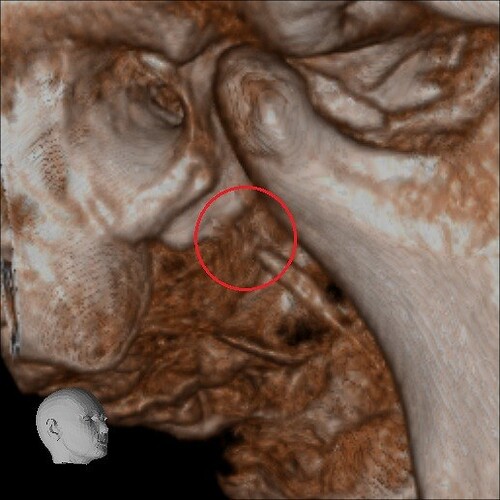

Below are some screenshots from my Cone Beam CT scan and the report linking possible ES. I have more Regular CT scans I could possibly share and/or if you would like me to get possible better angles from the Cone Beam CT scan let me know. But as of right now I’m at a loss as what to do going forward. I do have an MRI with and without contrast of the Cervical Spine Scheduled, but that’s due to the doctor’s (the doctor that dismissed it as ES and one doctor that wants to follow up and learn more on it) wanting it.

- Now onto this year, I finally got better back to full health in late November early December 2024 and sadly started to get another sinus infect in January and still no answers to why. I just happen to be watching YouTube when a Dentist had said that your teeth could be linked to sinus issues causing sinus infections and normally the only way to tell if this is the case is to get a Cone Beam CT scan. I then thought this could be another lead to find out why I keep getting sick as I did when I was 10 have my first top premolar on my left side removed against what I wanted as they said my teeth were too crowded and it needed to be removed so I could have braces (which that dentist didn’t even do my braces anyway). But I thought when he removed it if a small piece of the root was still in there as he just broke out the tooth without removing it via surgical means that that could cause an abscess in my Left Maxillary Sinus where infections always start. So, finally I was able to find a place that would give me a Cone Beam CT scan back in February of this year all while I was just starting to get sick from my infection. Anyway, I finally got the report in March and found out oddly my Left side is mostly normal other than mucus polyps, but I have a few other issues (I have attached the report below). This report is where I first found out about Eagle Syndrome as it states I might have Calcified Ligaments and further testing is needed to confirm. It was only after this report and looking up what Eagle Syndrome was that I can say I have almost every symptom that has ever been reported. Sadly, I couldn’t find anyone in my State at the time that work with Eagle Syndrome and when I did was about a week before I found this site and the doctor I did see seemed to dismiss me as another hypochondriac and you can’t have it as you don’t have Vertigo type Dizziness, my styloid are normal length and I don’t have neck pain equivalent to having to be in a neck brace. Not only this she only looked at my CT scan from a week earlier that I had got in Emergency. The Emergency visit was due to the fact at 8PM that night I had pain in my Right Mastoid Bone, and I was starting to get an earache. I went to lay down and took pain meds and an ice pack in hopes to reduce the pain and swelling. I couldn’t sleep due to the pain and came upfront about 10PM. 10:21PM I couldn’t take it anymore and started to stretch my neck and I felt a huge snap and heard a load pop, all the pain just felt like it disappeared. One minute later, I had a massive pain that spread just like when you get an IV that stings, but it felt like someone was trying to murder me and stabbed a knife into the right side of my skull. I was in so much pain that I was hunched over, and we had to have an ambulance called. I thought I was having an aneurism and my mother thought I was having a Stroke (very rare ES Symptom). When the ambulance arrived, they took my vitals, and my blood pressure was 148/110 with a pulse in the high 90’s low 100’s. Luckily the pain had subsided enough that we were able to go to emergency without the ambulance ride, but while I was in emergency the pain had spread to my left side of my head and now felt like someone had taken a clothes iron and stuck it on my head. Any breeze moving my hair was pure agony and I couldn’t lay my head on a pillow without that burning pain. According to emergency though I must have just had a Mastoid Process infection and it burst. Luckily the pain went away by the time I went to the Doctor for ES, but like I said before they were of no help.